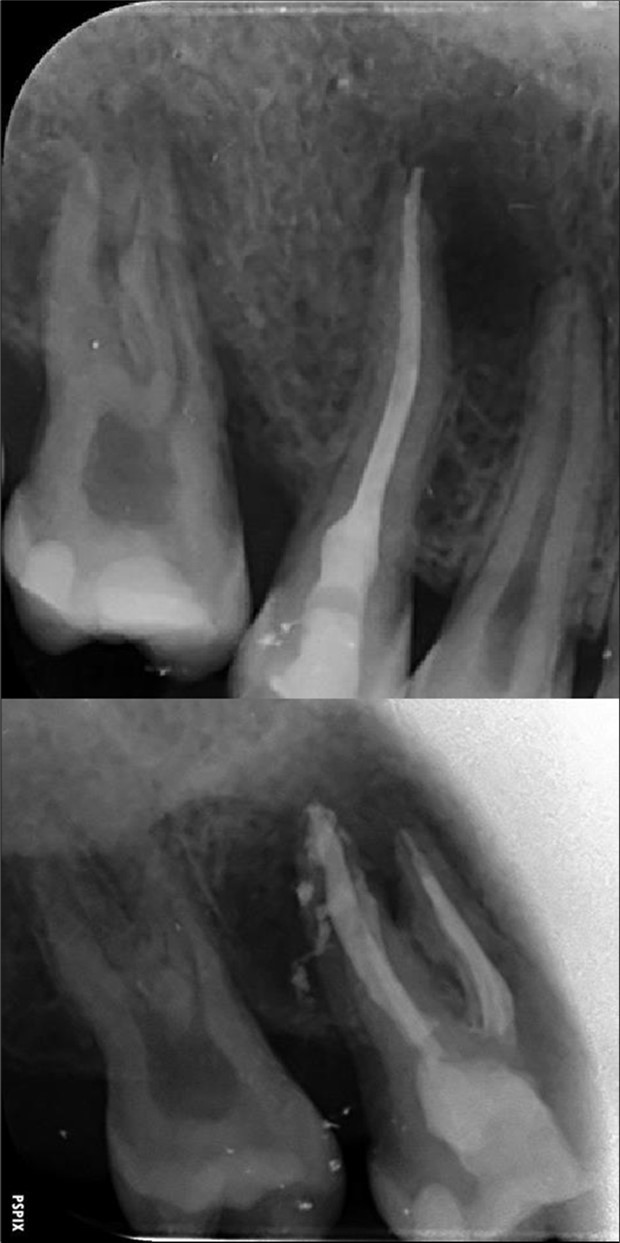

Periapical radiography (phosphorus number 2 plaque and X-MIND® Unity; Acteon) and cone-beam computed tomography (X-MIND® 3D; Acteon) (80 × 80, 150 Micron) were performed and showed periapical lesions on teeth 14, 15, 16, 24, 25, 26, 35, 36, and 46, as well as advanced endo-perio lesions on teeth 26 and 16. orthopantomogram (X-MIND® 3D; Acteon) and bitewings (phosphorus number 2 plaque and X-MIND® Unity; Acteon) also showed wide pulp chambers and roots canals. Figure 1, Figure 2

Figure 1.1 and 2 show a wide pulp chamber, root canals, and several restorations.

Figure 2.2. 3, 4, and 5 show periapical lesions on teeth 15, 16, 24, 25, 26, 35, 36, and 46.